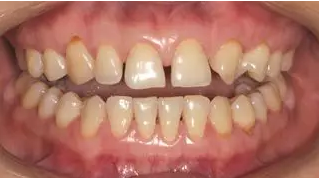

術(shù)前微笑照

病例分享|復(fù)合樹脂微創(chuàng)美學(xué)修復(fù)關(guān)閉上前牙間隙

術(shù)前全牙弓咬合照